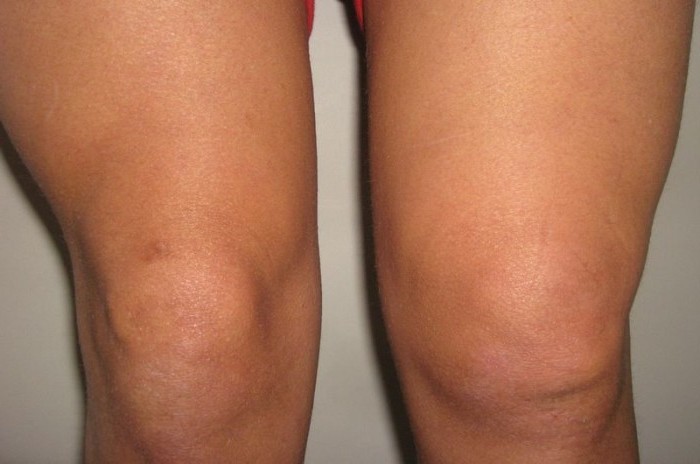

Остеоартрит коленного сустава второй степени проявляется яркой симптоматикой. На этой стадии патологический процесс сопровождается следующими клиническими признаками:

- Постоянные боли в области колена, усиливающиеся утром и вечером.

- Ограничение подвижности в коленном суставе.

- Замедленный темп ходьбы.

- Хруст в колене при движениях.

- Деформация суставных тканей, заметная невооруженным глазом.

- Признаки воспаления, включая отечность коленного сустава.

- Боль при пальпации колена и окружающих мышц.

На этом этапе мелкие фрагменты хряща или костной ткани могут попасть в полость пораженного сустава, что вызывает сильные боли и ограничение подвижности. Остеоартрит коленного сустава второй степени значительно ухудшает качество жизни и работоспособность пациента. Врачи отмечают, что именно на этой стадии лечение может быть наиболее эффективным и приносить наилучшие результаты.